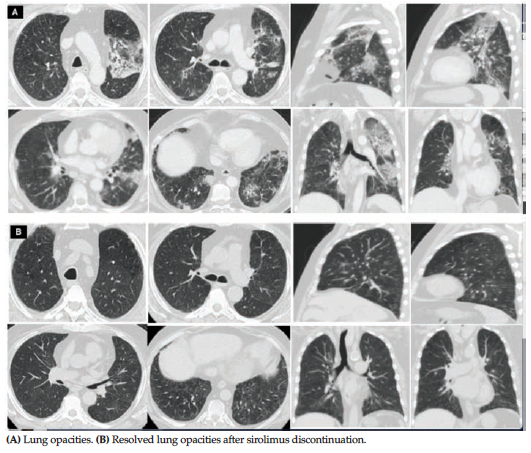

On examination, he had tachypnea and his oxygen saturation was 87% breathing room air. Auscultation of chest revealed basal fine crackles. Laboratory data showed normal white blood cell count but elevated C-reactive protein. A chest radiography and computed tomography (CT) scan showed multiple areas of ground glass and patchy densities (Figure 1A). Sputum culture was negative. Empirical broad-spectrum antibiotics did not show clinical or radiological response. An FDG-PET scan showed increased uptake in the area of lung opacities with standard uptake value of 4.7, indicating intense inflammation (Figure 2).

Serum sirolimus level was 8.5 ng/mL (therapeutic range, 4-11.9 ng/mL). Sirolimus levels in the weeks preceding admission for symptoms of lung toxicity were in the range of high normal (Figure 3A). After infections were ruled out, he was diagnosed to have sirolimus-induced lung injury. Sirolimus was discontinued and switched to tacrolimus. The patient continued to show clinical improvement, and his oxygen saturation became normal. On follow-up after 6 weeks, the patient was asymptomatic. A chest CT scan showed complete resolution of lung opacities (Figure 1B), and C-reactive protein level returned to normal (Figure 3B).

Figure 1. Computed Tomography Scan Results